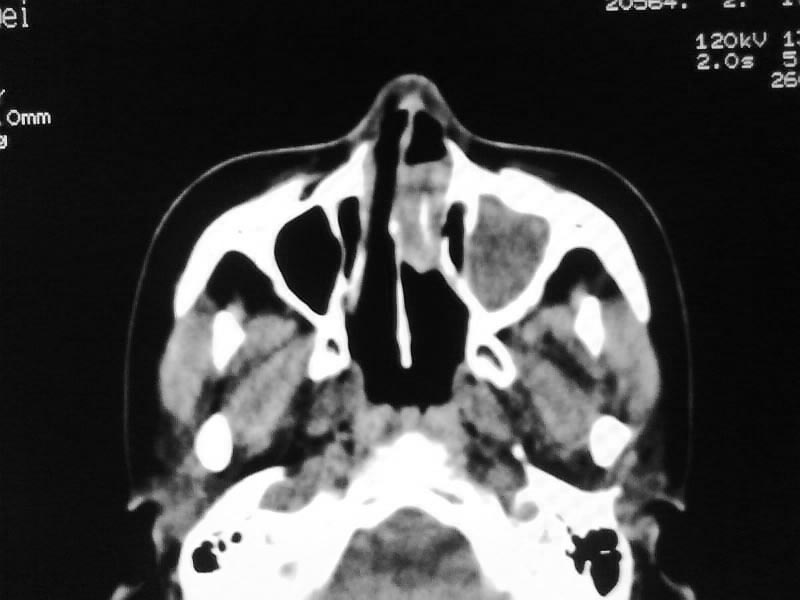

以下是引用zjzjr在2009-5-3 9:59:00的发言:[br]左侧鼻腔息肉、左侧筛窦、上颌窦炎症。双侧下鼻甲粘膜肥厚。

以下是引用随光逐影在2009-5-3 13:02:00的发言:[br]1)左侧鼻腔新生物(息肉可能)。2)左侧上颌窦及左侧筛窦炎症。3)双侧下鼻甲黏膜肥厚。